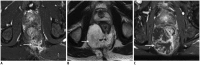

Although a rare disease, anal cancer is increasingly being diagnosed in patients with risk factors, mainly anal infection with the human papilloma virus. Magnetic resonance imaging (MRI) with external phased-array coils is recommended as the imaging modality of choice to grade anal cancers and to evaluate the response assessment after chemoradiotherapy, with a high contrast and good anatomic resolution of the anal canal. MRI provides a performant evaluation of size, extent and signal characteristics of the anal tumor before and after treatment, as well as lymph node involvement and extension to the adjacent organs. MRI is also particularly helpful in the assessment of complications after treatment, and in the diagnosis for relapse of the diseases.